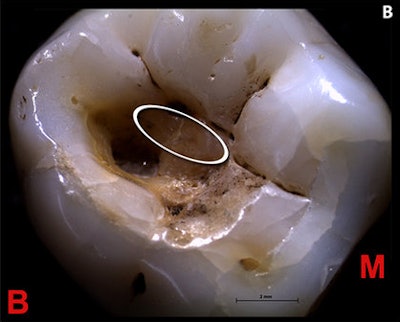

In this study, an international team of researchers analyzed a lower right third molar from a well-preserved 25-year-old male skeleton found in 1988 in a burial site in Villabruna, Italy. They discovered a tooth that retains a large occlusal cavity with four carious lesions.

Using a scanning electron microscope, the researchers identified striations and associated extensive enamel chipping on the mesial wall of the cavity, which they suggested were made by pointed flint tools during scratching and levering activities while the young man was alive.

"Various scientific analyses confirm that the vast carious lesion found on the chewing surfaces of the lower right third molar was intentionally treated, probably to clean out the infected tissue, through the use of a stone tip that left deep streaks on tooth enamel around and inside the cavity," said Jacopo Moggi-Cecchi, an associate professor from the department of biology at the University of Florence, in a statement.

The orientation of the individual traces within the cavity indicates that a variety of gestures and movements associated with the slicing of the tool edges in different directions were used, they noted. The marks were potentially made during back and forth, semicircular, levering, and scratching movements, according to the researchers.